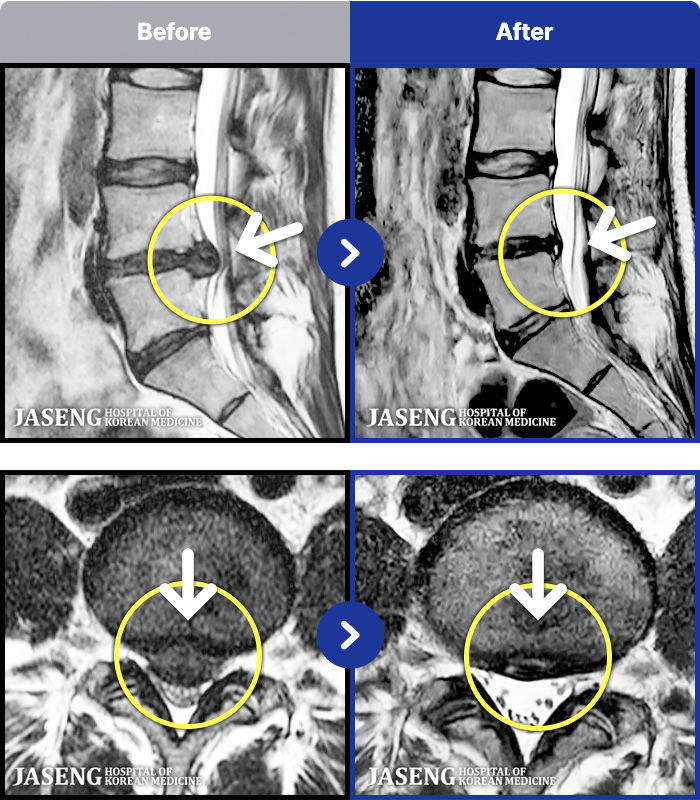

- MRI ġ

MRI ġ

191 MRI ũ ʸ Ȯϼ.

[Կñ:25.07.07~26.03.10]

[_㸮ũ] ؽ ð ɾ ְų ִ ڼ ¿.